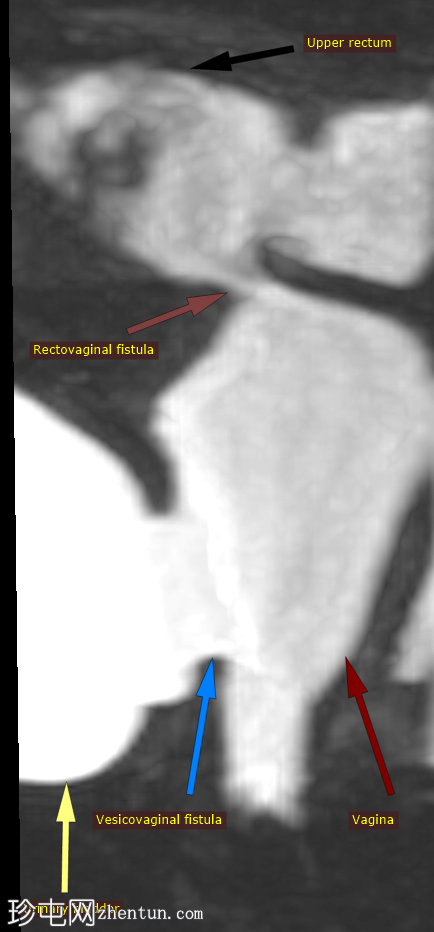

膀胱阴道和直肠阴道瘘

患者主诉尿失禁和阴道分泌物增多,既往有手术史和结肠造口术史。

年龄:35岁

性别:女

膀胱后壁与阴道前壁之间存在宽阔的瘘管。膀胱内可见气液平面。

膀胱充盈前,该影像无法显示阴道后穹窿上缘与直肠中段前壁之间较小的瘘管。

图示

9.png

这张三维重T2加权重建图像在同一张图像中同时显示了膀胱阴道瘘和直肠阴道瘘,从而可以同时观察到两条独立的瘘管。

本病例显示了一个医源性膀胱阴道瘘。

此外,还有一个较小的直肠阴道瘘,容易被忽略,但直肠扩张并伴有液体信号强度(未注射凝胶)提示存在直肠阴道瘘。给予患者饮水以充盈膀胱,薄层扫描清晰地显示了狭窄的瘘管。

当膀胱未完全充盈时,直肠阴道瘘不明显,直肠内液体量也很少。然而,膀胱充分充盈后,直肠扩张,瘘管清晰可见。这凸显了在怀疑存在短瘘时,通过注入外源性液体或增加口服液体摄入量等方法确保操作技术正确的重要性,正如本病例所示。